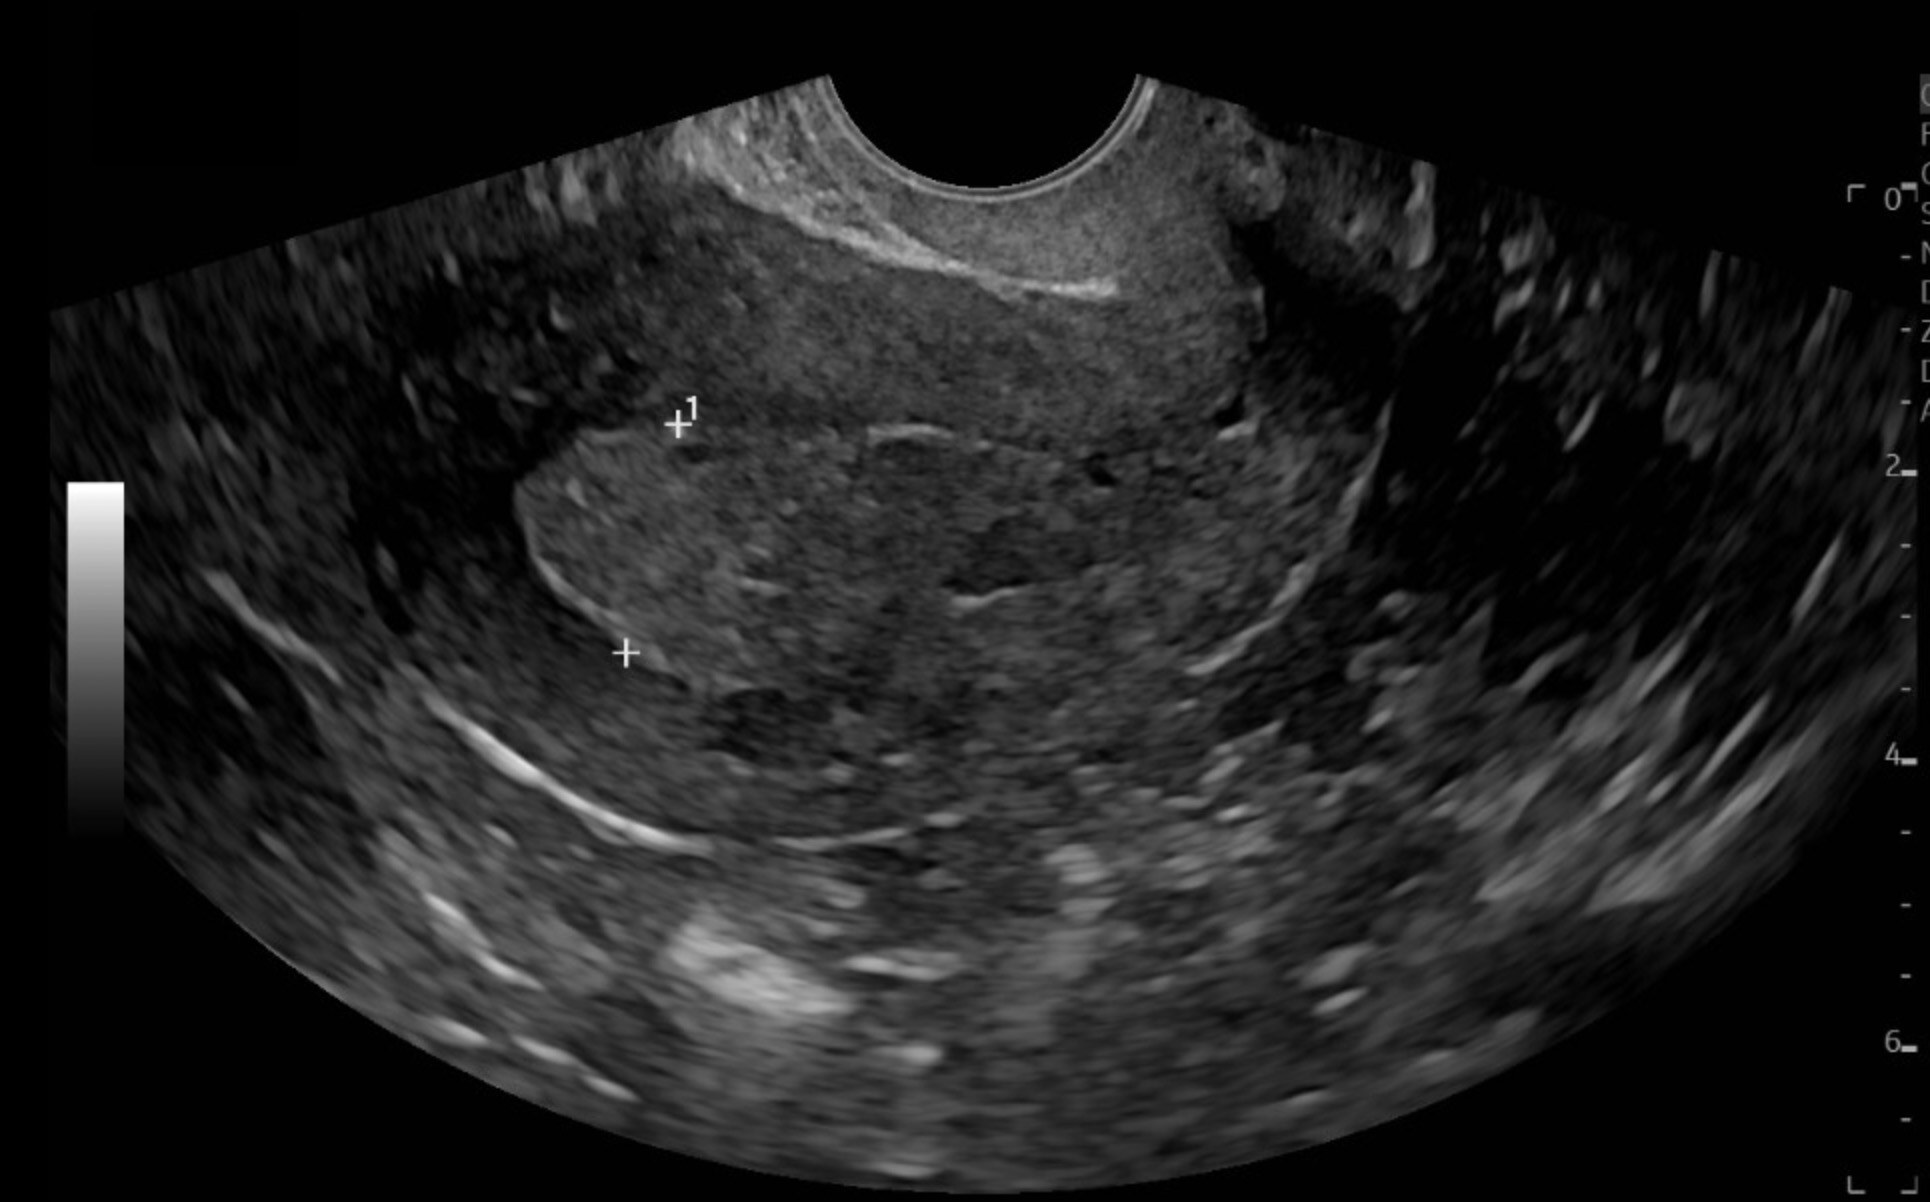

Although the majority of endometrial malignancies are due to endometrial hyperplasia, it should be noted that a number of tumors, including uterine serous carcinoma, are not associated with prior endometrial hyperplasia.6 Endometrial carcinomas can produce an increased risk of HMB, but they also are more often associated with an irregular and continuous bleeding presentation and, thus, more likely to present as AUB.6 TVUS is considered a first-line screening tool to assess endometrial thickness, particularly in postmenopausal women with bleeding. (See Figure 2.) An endometrial thickness ≤ 4 mm has a high negative predictive value for endometrial cancer, but a thickened endometrium is not diagnostic and requires histologic evaluation. However, recent studies have shown that it is not a reliable tool for up to 11.4% of cases with endometrial cancer.28 Computed tomography (CT) scans typically are not effective for initial diagnosis of endometrial carcinoma.27 Patients with concerning features for endometrial cancer — such as advanced age, previously mentioned risk factors, and/or a thickened endometrial stripe on TVUS — should be referred to gynecology for further evaluation and endometrial biopsy.28 Ultimately, a conclusive diagnosis depends on biopsy of an endometrial tissue sample.27

Figure 2. Transvaginal Ultrasound Demonstrating a Thickened Endometrial Stripe, Concerning for Endometrial Cancer |

![]() |

Image courtesy of Daniel Migliaccio, MD. |